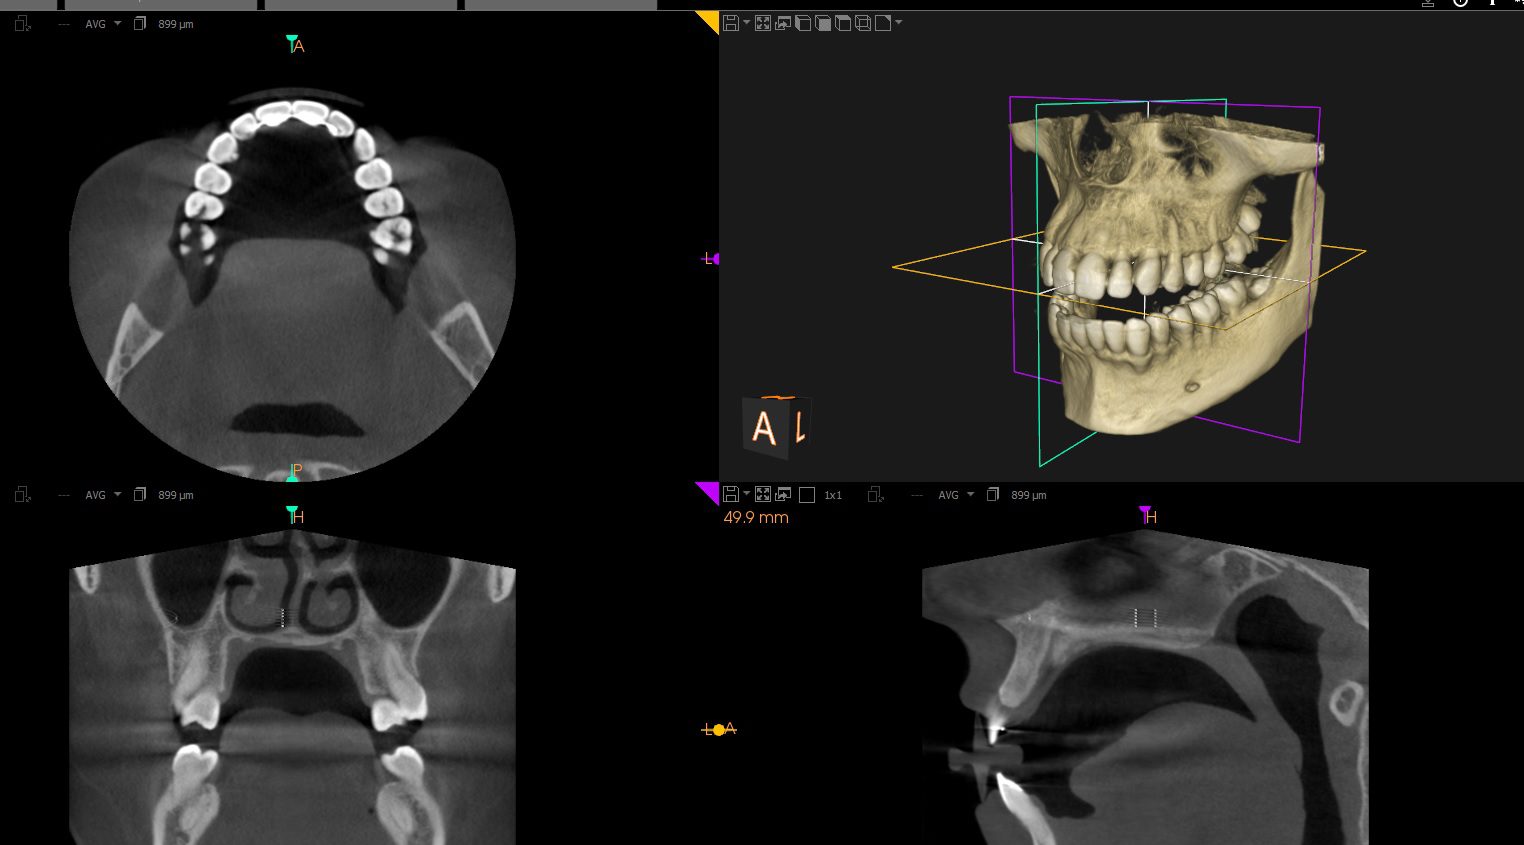

La radiología 3D también se conoce como tomografía computerizada (TC) dental. A diferencia de las radiografías convencionales, que sólo proporcionan imágenes en dos dimensiones, la TC dental crea una imagen tridimensional de boca y mandíbula. Esta tecnología avanzada utiliza rayos X para tomar múltiples imágenes en capas muy finas, que después se combinan para crear una imagen en 3D.

Los beneficios de la radiología 3D son múltiples. Por ejemplo, los odontólogos y odontólogas pueden utilizar esta tecnología para planificar mucho mejor los implantes dentales, ya que pueden visualizar con precisión la estructura ósea de sus pacientes. La radiología 3D también puede ser útil en la planificación de tratamientos de ortodoncia, ya que los ortodoncistas pueden ver exactamente cómo los dientes se ajustan y cómo se mueven a lo largo del tiempo.

Además, la radiología 3D puede detectar previamente enfermedades en las etapas iniciales, lo que permite un tratamiento más temprano y efectivo. Por ejemplo, la tecnología puede detectar tumores dentales, quistes y otros problemas que no son visibles en una radiografía convencional.